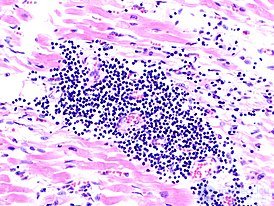

1. Воспаление миокарда.

воспаление сердечной мышцы.